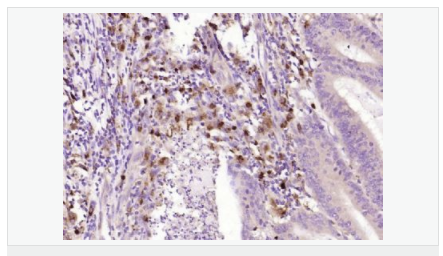

| 產(chǎn)品應用 | WB=1:500-2000 ELISA=1:5000-10000 IHC-P=1:100-500 IHC-F=1:100-500 ICC=1:100-500 IF=1:100-500 (石蠟切片需做抗原修復) not yet tested in other applications. optimal dilutions/concentrations should be determined by the end user. |